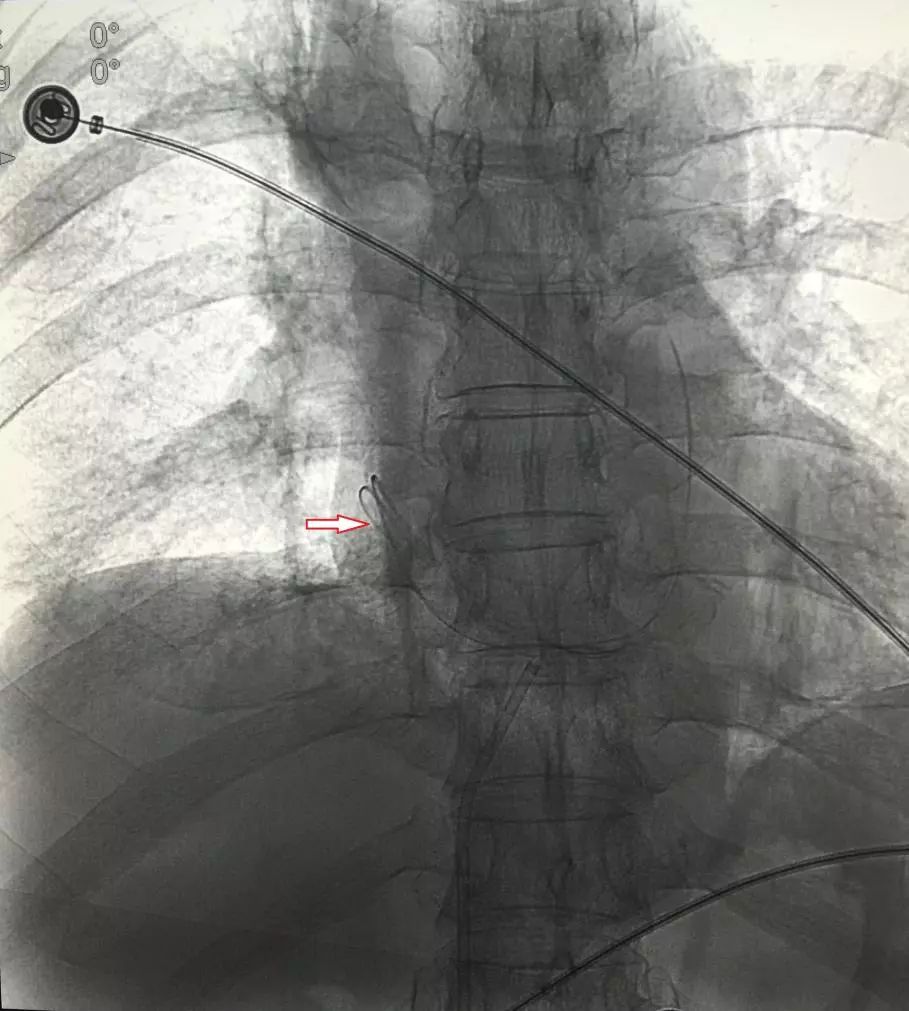

手术中,宋太民主任带领副主任医师刘刚、主治医师刘要先将取异物装置经股静脉、下腔静脉顺利置入右心房,通过透视发现导管显影较差,只有贴近造影显示屏才能隐约看到异物相互缠绕,导管头端位置更是难以确定。

▲DSA下心脏中PICC残管显影

由于患者心理紧张,手术期间心率一度达到150次/分钟以上,宋太民主任不仅观察病情,更观察着患者的一举一动,时时俯身下来询问老人情况,不停地在耳边安慰着他,老人的紧张情绪慢慢得到了缓解,安慰好老人后,宋太民操纵着抓捕器成功套住导管头端,缓慢回撤,取出一根约40厘米长的PICC置管。拔管后加压止血包扎,造影见右心房、肺动脉显示良好,无异物影,手术顺利。